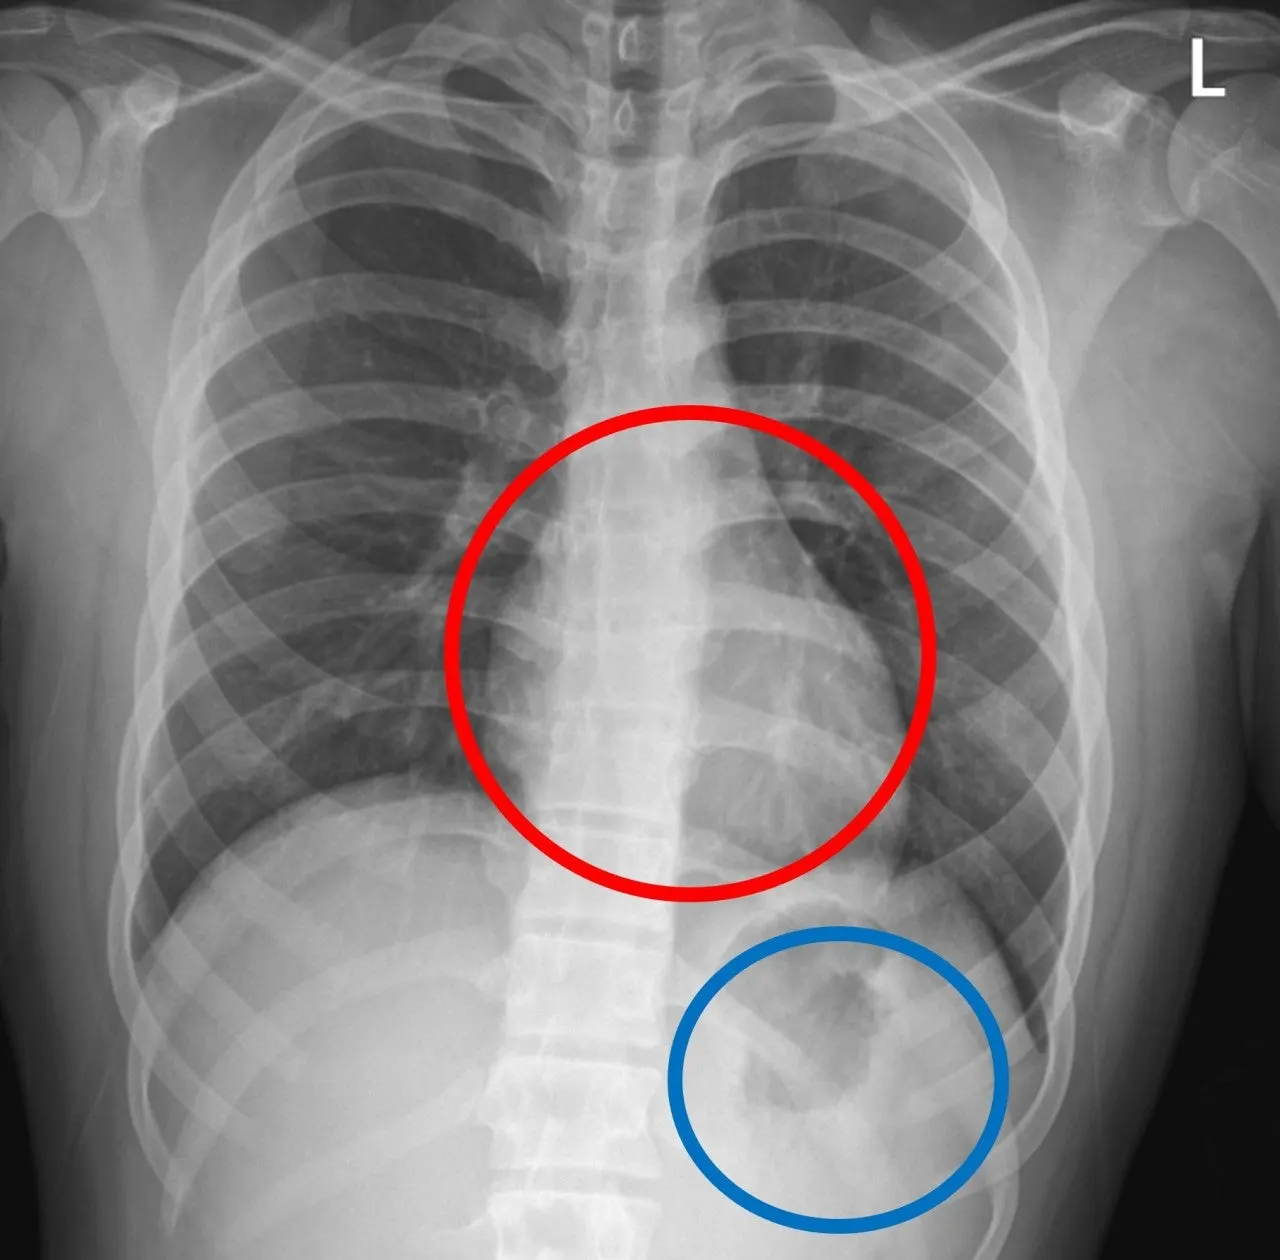

“저 하얀거(주황색 동그라미) 뭐예요?”

“저기 저거요? 저건... 거품입니다.”